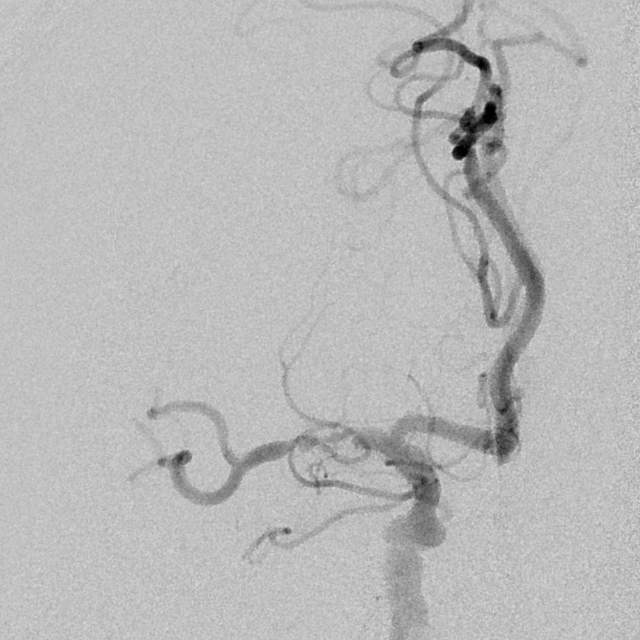

78岁老年男性,最近一个半月来已经和家里人没法正常交流,认知能力大幅下降,在农村,可能也就认为年龄大了,听天由命了。可老人家就是福大命大,有亲戚做医生,间隔17天先后为老人做了两次头颅MRI,发现脑梗塞,右侧血管长节段严重狭窄,右侧大脑半球缺血严重(图6,满江红),手术风险大……,家属经过反复咨询、犹豫、权衡,选择了保守治疗,毕竟老人年龄大了,手腿现在还能动,手术也有风险,时机也不是太好,国外研究不推荐,国内研究也不支持,保守治疗似乎是个不错的选择。然而,保守期间,患者反复出现脑梗塞,认知能力进行性下降,最终促使家属决定采用外科干预。然而,对医生而言,在梗塞的急性期处理这种长节段密布分支血管的病变风险不言而喻,而一味的观望和等候肯定不是最佳选择。过一点,可能出血;欠一点,可能闭塞。全面认真评估后,我们顺利为老人家完成了I期治疗,老人家的“火焰山”(图6)变成了“绿油油”充满生机的田野(图14),缺血明显改善,认知能力大幅提高,术后就能和家人正常交流了,也记起了很多以前忘记的事情……,家人很开心。